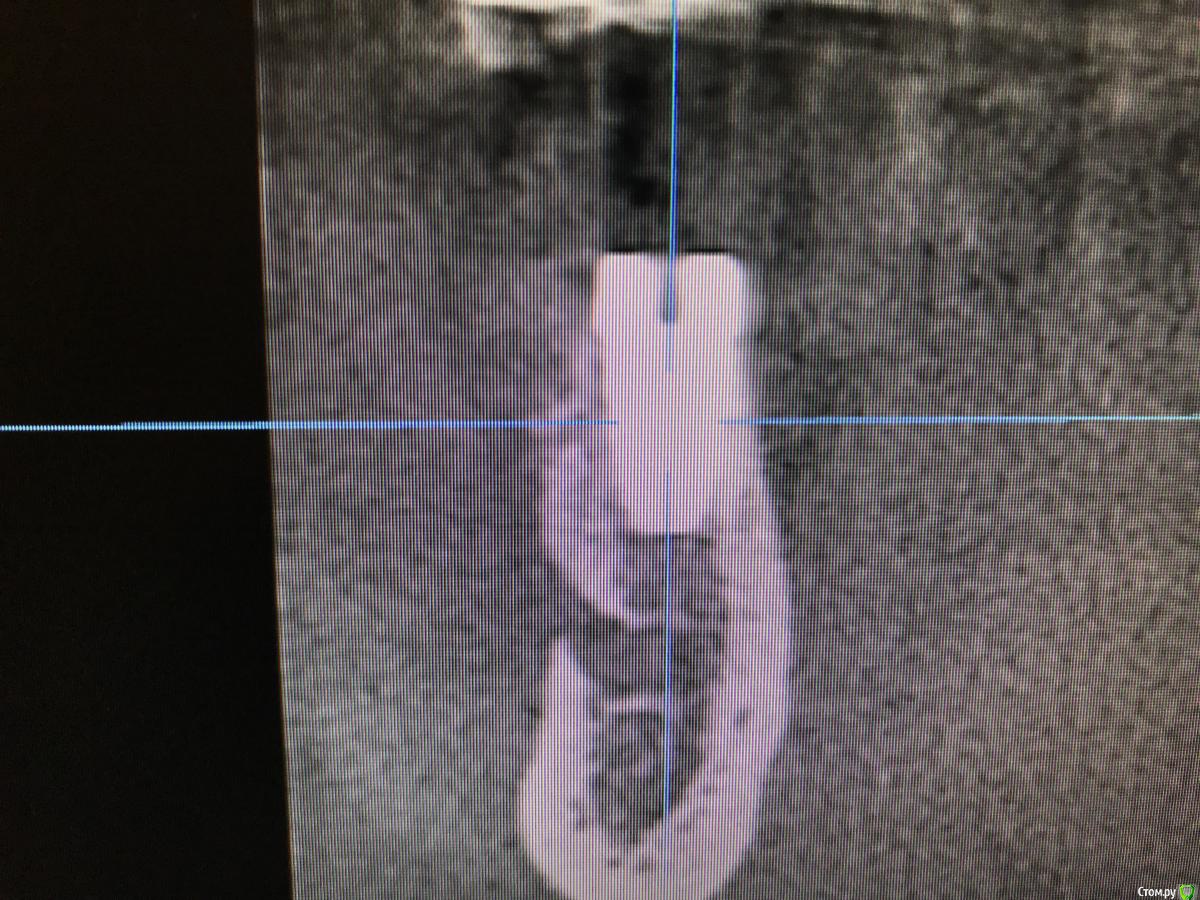

колесников Опубликовано 27 сентября, 2019 Автор Поделиться Опубликовано 27 сентября, 2019 Улучшение объема и качества мягких тканей в пришеечной области у ранее поставленных имплантов ,посредством тоннельной костной пластики. Объём 0,5г. Вид через 6 мес. 3 Ссылка на комментарий